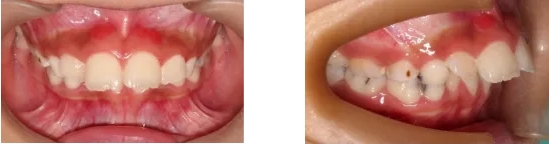

患兒9歲,前牙反合,右側(cè)上下第一恒磨牙正鎖合。前牙反合會限制上頜骨發(fā)育,影響患者咀嚼功能、顏面美觀及心理健康,后牙正鎖合會影響下頜骨正常運動及顏面發(fā)育,導(dǎo)致顳下頜關(guān)節(jié)病變及顏面美觀。經(jīng)過半年的治療,患兒前牙達到正常覆合覆蓋,后牙正鎖合得到解除。患兒面型也得到改善。